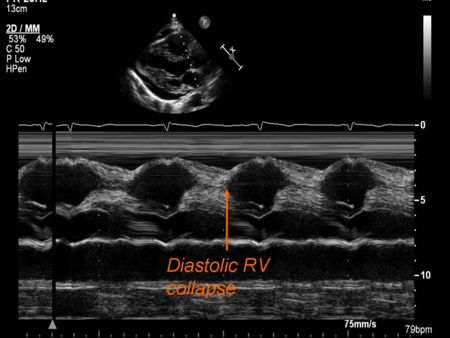

M Mode in Tamponade

- Diastolic collapse of the right ventricle